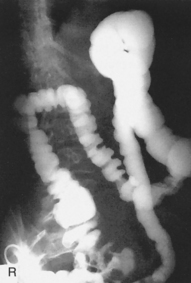

The air-barium distribution within the stomach and large intestine changes with various body positions. By knowing these distribution patterns, one can determine in which body position a radiograph was taken. Air always rises to the highest levels, and the heavy barium settles to the lowest levels (air is black, barium is white).

The fundus is located more posteriorly; therefore in the supine position it would be the lowest portion of the stomach and would be filled with barium.

In both prone and erect positions, the fundus would be filled with air as seen on the drawings below, with a straight air-barium line on the erect.

The ascending and descending portions are located more posteriorly, and thus more of these parts in general would be filled with barium (white) in the supine position and with air (black) in the prone position.

This much separation of barium and air occurs generally only with double-contrast barium-air studies.

Air-fluid levels would be seen in the erect position in which the air would rise to the highest position in each of the various sections of the large intestine, as shown in the accompanying figure.

Right and left decubitus projections (not shown on these drawings) also would demonstrate air-fluid levels, with air again rising to the highest portions.